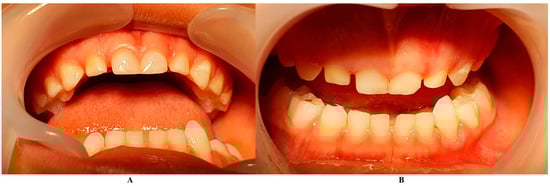

Figure 4.

Tooth loss (September): (A)—alveolar socket with no inflammation signs, (B,C)—tooth with root apical third resorptive signs and traces of calculus and dental plaque in the root cervical area and middle third (the potential origin of the periodontal problems).

Eventually, as expected, the tooth was lost at the beginning of September, and alveola healed without further problems (Figure 4).

The bacterium types present in this case (i.e., Fusobacterium nucleatum/periodonticum and Capnocytophaga spp.) were reported not to produce ATP molecules [13]; nevertheless, the presence of Fusobacterium nucleatum has been reported to be associated with a high number of late colonizers associated with periodontal destruction [12,13], which might explain some of the localized aggressive periodontal destruction. Nevertheless, on the lost tooth (Figure 4B,C), some traces of calculus and plaque are visible, confirming the source of periodontal bacteria.

Retrospectively speaking, the tooth showed visible traces of plaque and calculus deposits (Figure 4B,C), which could be present on the tooth throughout the infectious episode, going unnoticed, and representing the original source of bacteria. Nevertheless, it must be emphasized that full professional scaling and root planning was extremely difficult in this case, due to the child’s small age and problems of collaboration (hence the importance of individualizing periodontal treatment).